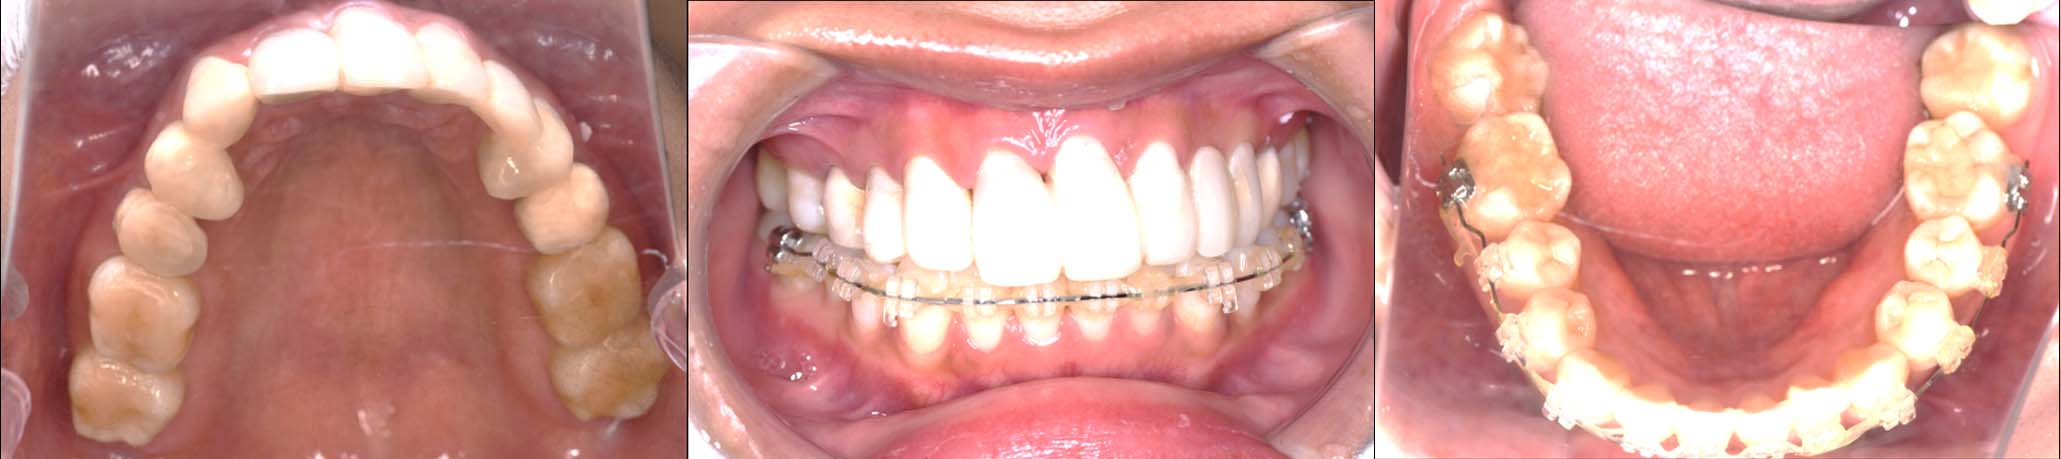

噛み合わせ治療の症例24

スプリント使用後、

補綴治療をした症例

| 治療内容 | ①スプリントを装着 ②副子を装着 ③2024年4月 口腔内反映開始 ④副子を入れた状態の所まで咬合を挙上 (バイトアップ) ⑤2024年5月 上顎前歯部8本へ仮歯(TEK) を装着 |

バイトアップ後

2024年 10月 下顎MTM開始